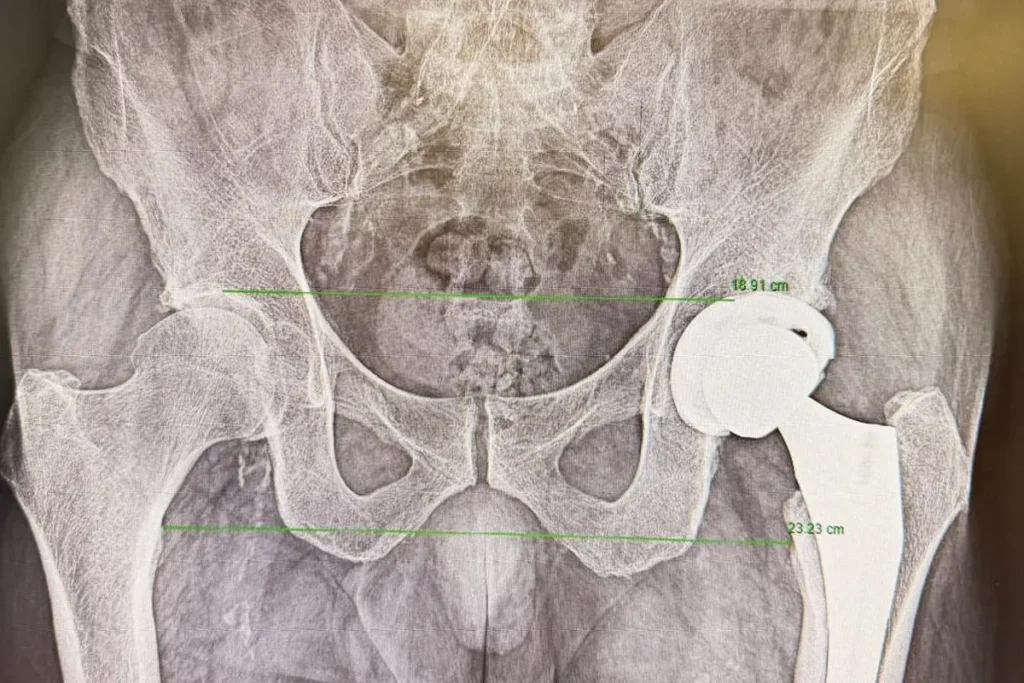

En tal procedimiento, se seleccionan a pacientes con dolor persistente al caminar, una rigidez que limita gestos cotidianos o la pérdida progresiva de autonomía. Todas ellas son las consecuencias más visibles de la artrosis avanzada de cadera, fracturas complejas o determinadas deformidades articulares.

La otra clave que debería tranquilizar a los pacientes que se someten a una cirugía de prótesis de cadera se explica por la evolución de las técnicas quirúrgicas. La llamada vía anterior en la prótesis de cadera, aunque no es nueva, ha ganado popularidad en los últimos años por sus ventajas en el postoperatorio inmediato. A diferencia de otros abordajes, permite acceder a la articulación entre planos musculares, sin necesidad de seccionar músculos. “La gran ventaja de la vía anterior es que el paciente tiene menos dolor en los primeros momentos tras la cirugía y puede iniciar antes la movilización”, explica el doctor Martín Buenadicha. Esta menor agresión muscular favorece un inicio más temprano de la fisioterapia y de la marcha, elementos clave cuando se plantea un alta en el mismo día.

A medio y largo plazo, los resultados funcionales suelen equipararse con los de otras vías quirúrgicas. No obstante, esa recuperación inicial más ágil resulta determinante en el contexto ambulatorio. Poder levantarse pocas horas después de la intervención, caminar con ayuda y controlar adecuadamente el dolor marca la diferencia entre un ingreso convencional y un regreso seguro al domicilio.